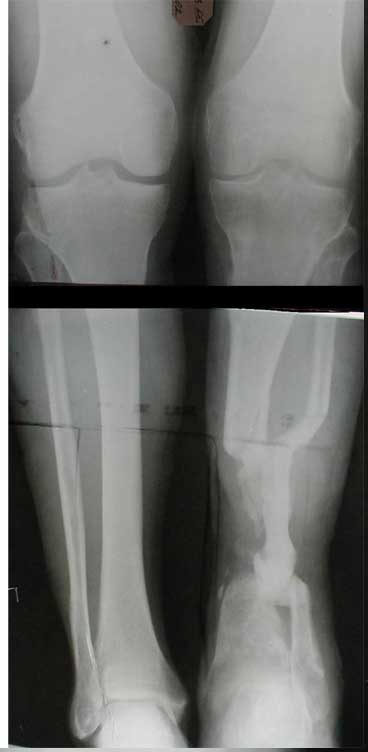

Вы абсолютно правы, что абсолютных показаний к ампутации нет. И как говорится "клиент всегда прав".

К сожалению на первичной и последующей рентгенограммах не видно, что творится с голеностопным суставом. Если вилка суства сохранена, то есть смысл побороться за конечность. Интересно, увитеть, что твориться с голеностопным суставом.

В любом случае желаю удачи.